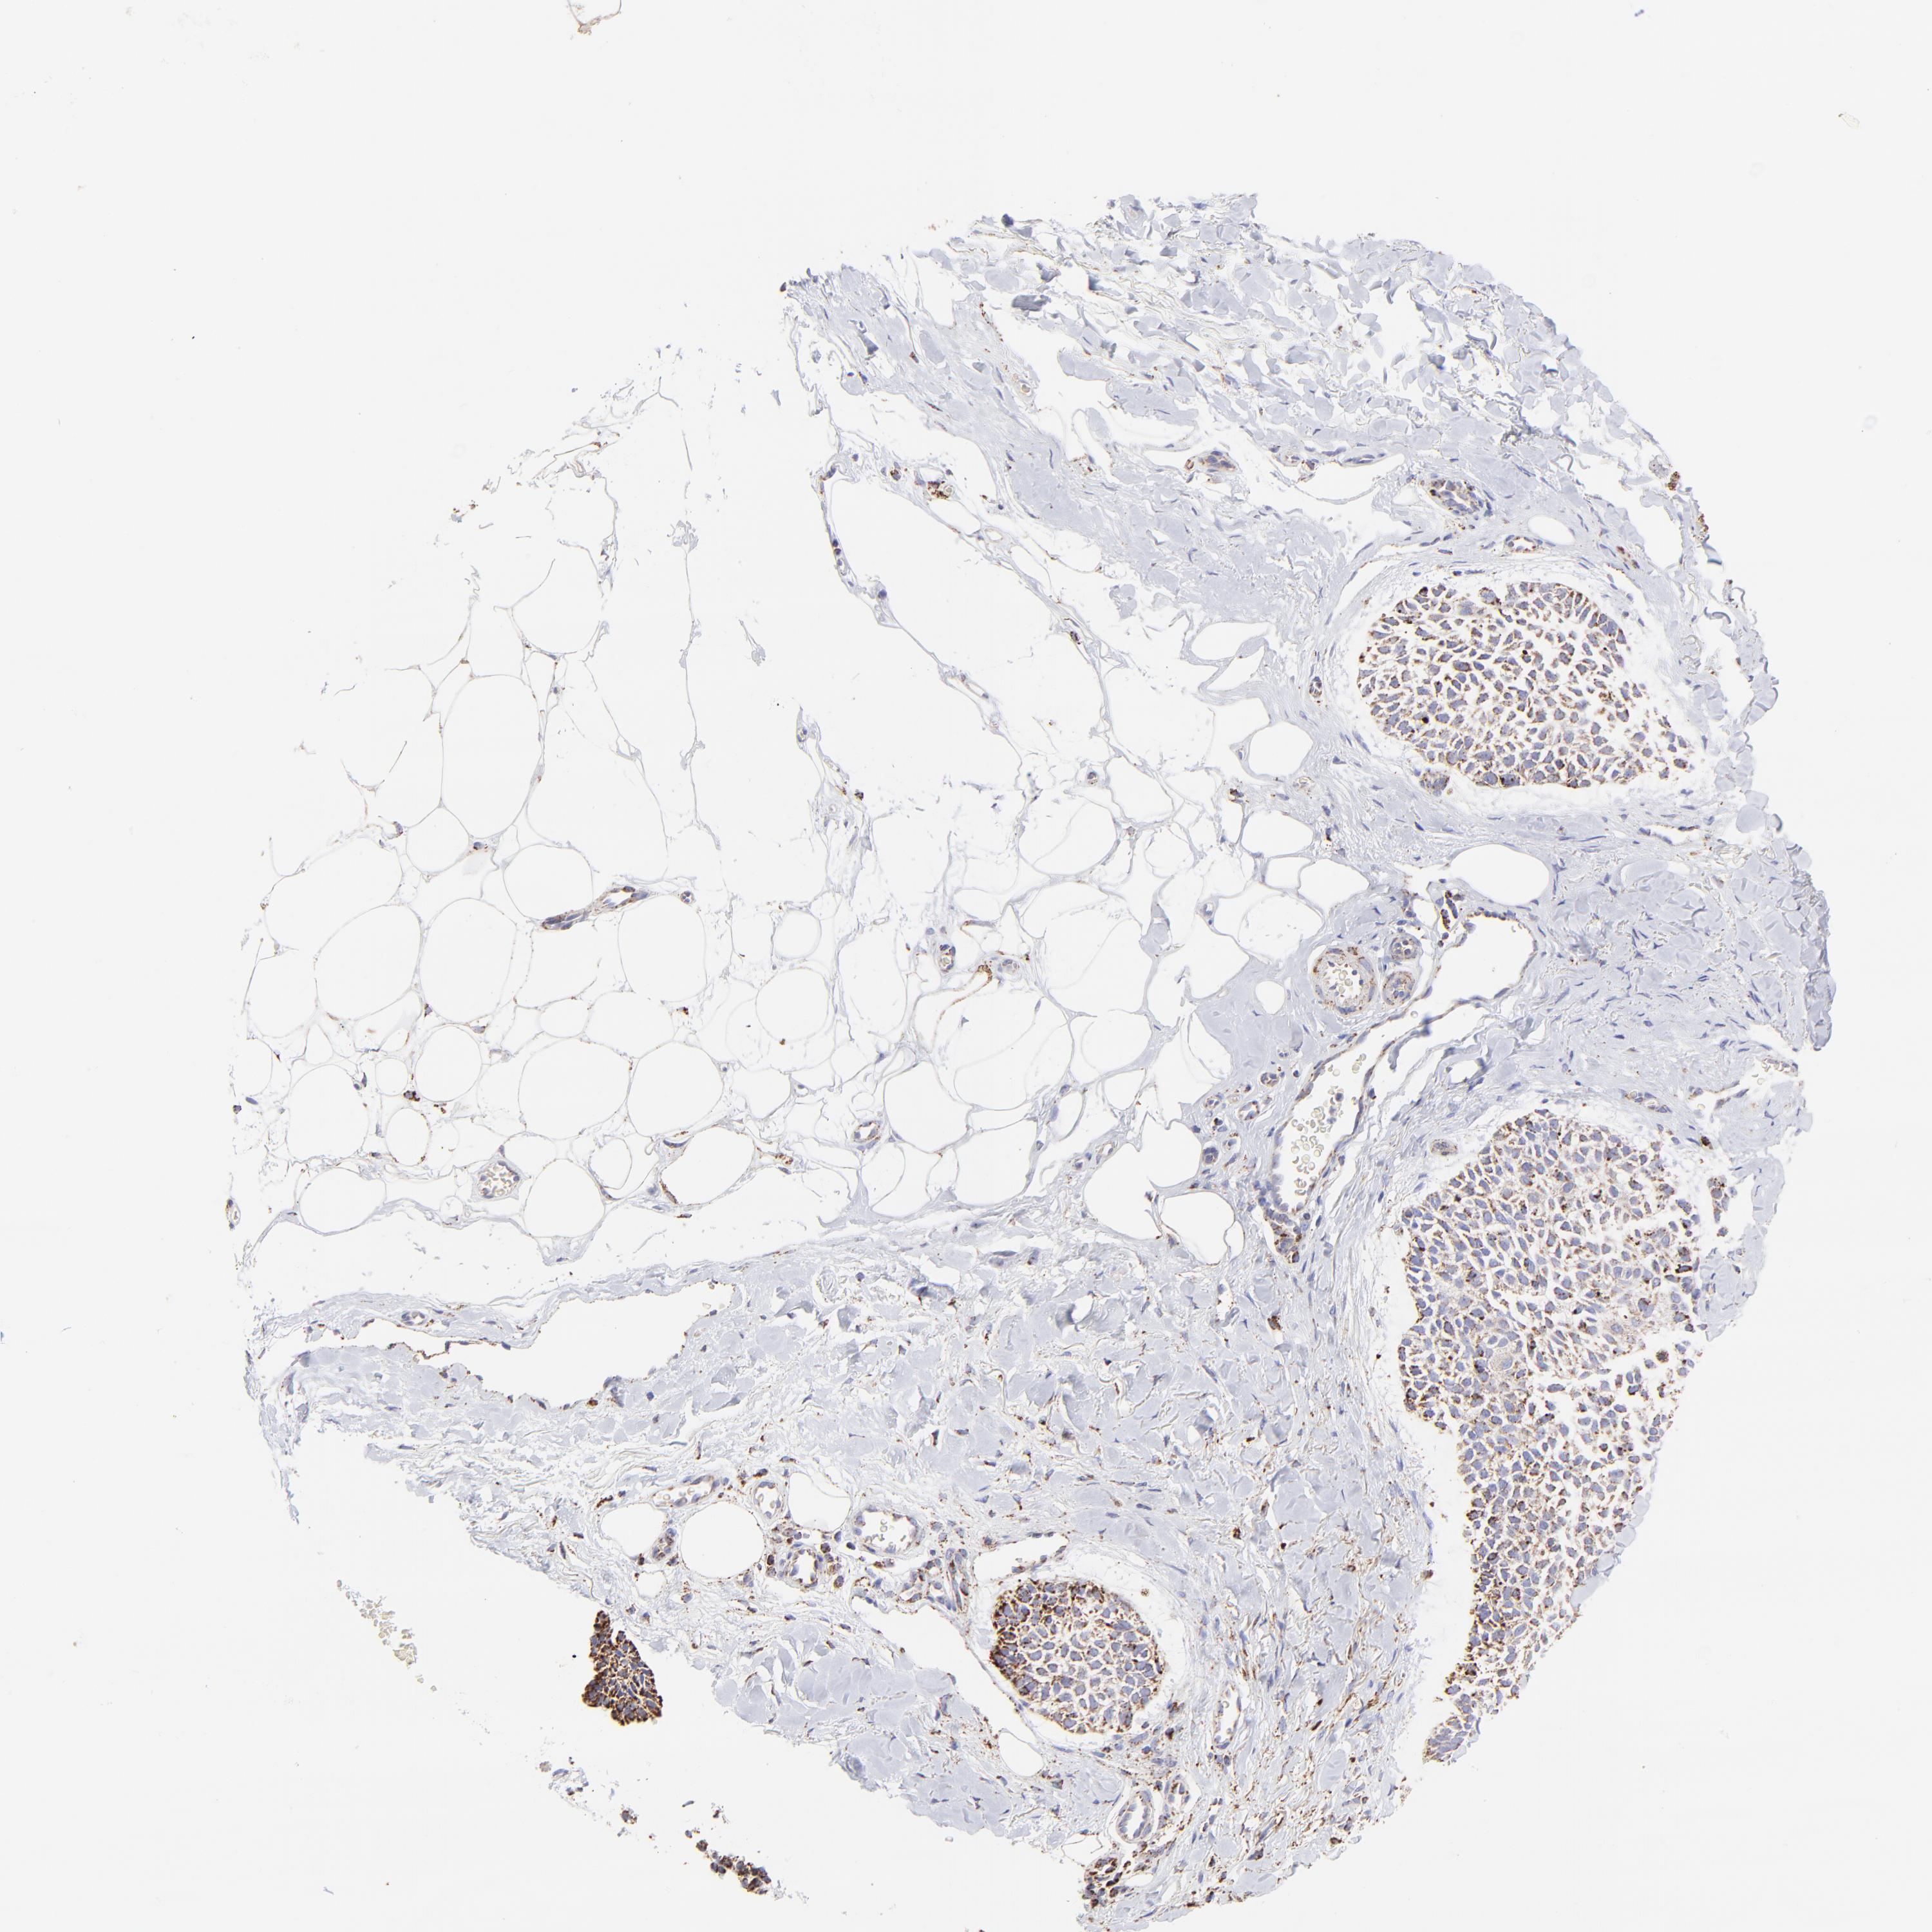

SKIN CANCER - Protein expressioni

A mouse-over function shows sample information and annotation data. Click on an image to view it in a full screen mode. Samples can be filtered based on level of antibody staining by selecting one or several of the following categories: high, medium, low and not detected. The assay and annotation is described here.

Antibody stainingi

Antibody staining in the annotated cell types in the current human tissue is reported as not detected, low, medium, or high, based on conventional immunohistochemistry profiling in selected tissues. This score is based on the combination of the staining intensity and fraction of stained cells.

Each image is clickable and will lead to virtual microscopy that enables deeper exploration of all samples and also displays staining intensity scores, fraction scores and subcellular localization as well as patient and tissue information for each sample.

Antibody HPA002907

Antibody HPA005835

Staining

High

Medium

Low

Not detected

Intensity

Strong

Moderate

Weak

Negative

Quantity

>75%

75%-25%

<25%

None

Location

Nuclear

Cytoplasmic/membranous

Cytoplasmic/membranous,nuclear

Squamous cell carcinoma, NOS

Basal cell carcinoma